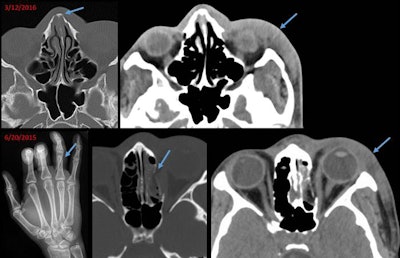

One unfortunate story -- of a young woman with an acute nasal bone fracture that was superimposed on a previously healed fracture -- spurred the researchers to investigate common characteristics of domestic violence as they appear on radiological images.

Bone remodeling, deformity, and focal bone thickening are telltale signs that can distinguish old, healed fractures from acute fractures, said Dr. Bharti Khurana, director of the emergency radiology fellowship program at Brigham and Women's Hospital. The presence of both old and acute fractures on radiological images could play a vital role in the diagnosis of intimate domestic violence.

In addition, the researchers identified various patterns of injury, including soft-tissue injuries, fracture in the distal upper extremities, and facial fractures.